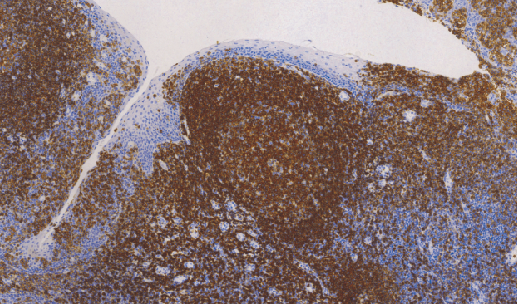

CD45R是CD45的同源异构体之一,分子量为220KDa,表达于B细胞、单核细胞和少量的T细胞、此抗体可以识别大多数的B细胞及B细胞淋巴瘤,此抗体与其他B细胞抗体联合使用,主要用于B细胞淋巴瘤的研究。

- 阳性部位:胞膜

- 适用组织:石蜡切片

- 预处理:热修复